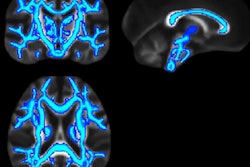

The approach uses functional MR elastography (fMRE) to create maps of tissue stiffness, which, in turn, track the activity of brain function that occurs in bursts as short as 100 msec. Early indications are that fMRE could be better than functional MRI (fMRI), because fMRI cannot keep pace with the split-second activity of the brain's neurons as they process thoughts and react to various stimuli.

"Traditional fMRI has a temporal response of several seconds and, therefore, cannot measure high-level cognitive processes that evolve in tens of milliseconds," wrote author Samuel Patz, PhD, from Brigham and Women's Hospital in Boston, Massachusetts, U.S., along with colleagues from King's College London in the U.K. and the French National Institute for Health and Medical Research (INSERM) in Paris. "To advance neuroscience, imaging of fast neuronal processes is required. Here, we directly show in vivo imaging of fast neuronal processes at 100-msec time scales by quantifying brain biomechanics noninvasively with MR elastography."

The brain's stiffening and softening responses were replicated on subsequent fMRE scans under different types and levels of stimuli. At 100 msec of stimulation, there also were changes in the thalamus, which is "the relay location [for] input to the cortex," the authors noted.